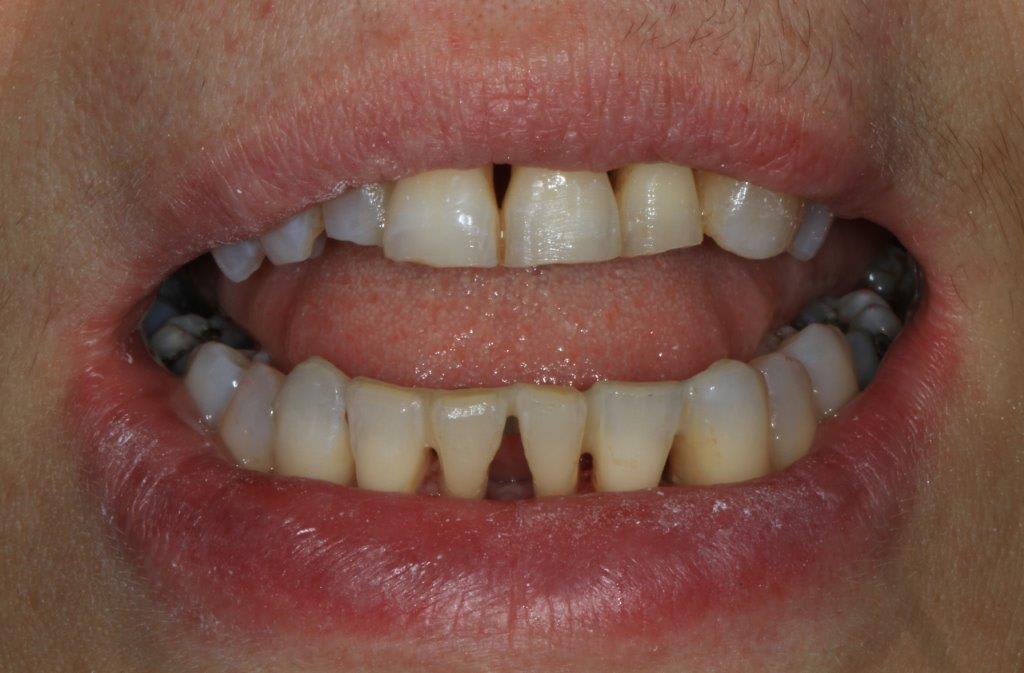

un peu de grain à moudre, toutes les critiques sont les bienvenues...

1ere séance,"nettoyage...", et après réflexion, plutôt que le nettoyage par le vide, attelle de contention pour le bloc antérieur mandibulaire, suppression de quelques contact très parasite sur les pm et canines, et réduction des incisives mandibulaire puis maxillaire... consignes de brossages / bain de bouche avec .... l'érythritol afin de ne pas mourir idiot... on verra ce que ça donne dans un cas relativement perdu d'avance.... merci Algi... enfin peut être : -))

C est dommage que l'on ne voit pas les dents en occlusion .

La 12 est en occlusion inverse et le secteur postérieur 20/30 aussi ?

" pcq ce truc ressemble comme 2 gouttes d eau à la résultante d' un sur contact antérieur de type cl2 associé à un décentrage latéral post unilatéral . à

gauche probablement ."

Une fois de plus ce n est pas un pb Paro mais bien occlusal .

effectivement, je vois la conséquence paro d'un problème avec départ occlusal, mais peut être pas que.

le soucis est de résoudre l'équation, qui ne passera pas que par une équilibration, un peu comme si un cancer de la vessie, chez un patient fumeur, se soignait uniquement en arrêtant le tabac.